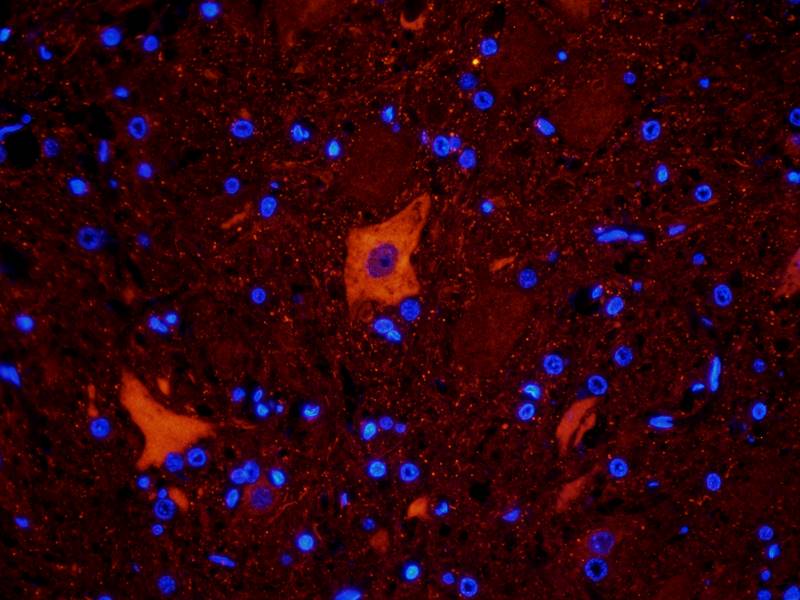

IHC staining of FFPE human brain with Ubiquitin antibody (clone PBQN-1). Required HIER: boil tissue sections in pH9 10mM Tris with 1mM EDTA for 10-20 min followed by cooling at RT for 20 min.